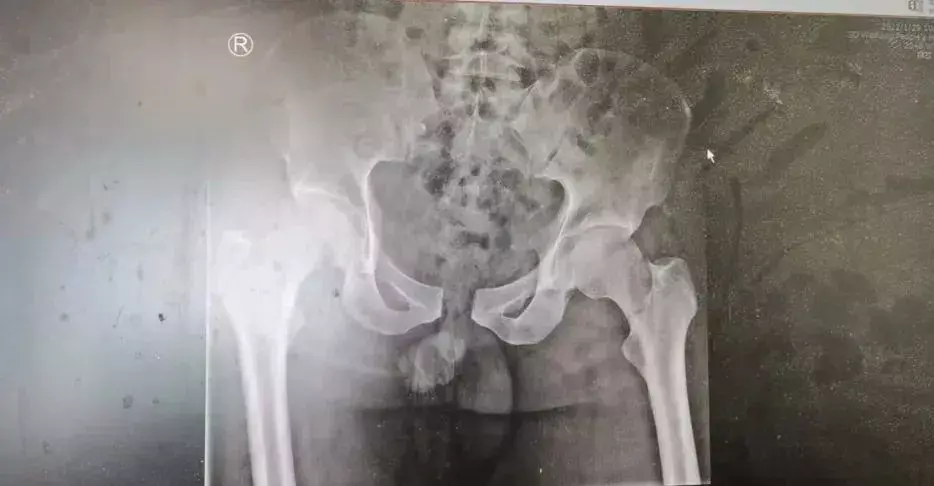

手术中

经过周密的术前准备,孙学成带领团队为患者实施了手术,整个手术过程持续了5个小时。手术中,首先将坏死挫伤的皮肤、皮下筋膜、肌肉等软组织及游离的碎骨块进行了彻底的清创;患者左膝关节损伤严重,缺血时间长,综合评估后无法行进一步手术,给予股骨远端截肢处理;右小腿清创后,大面积骨外露,软组织缺损,按照预案将残肢的足背皮瓣切取,覆盖右小腿胫前内侧皮肤缺损,采取皮瓣技术修复了小腿的创面。患者的右腿成功地保住了!